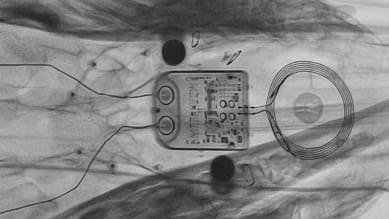

ABILITY enters preclinical trial

A preclinical trial is underway with the ABILITY brain-computer interface system.

The study, which is being carried out in sheep, is a crucial step towards development of a fully implantable device to enable applications such as communication and movement for people with paralysis.

The trial will assess the safety and feasibility of brain signal recording and wireless transfer of neural data to a wearable computer.